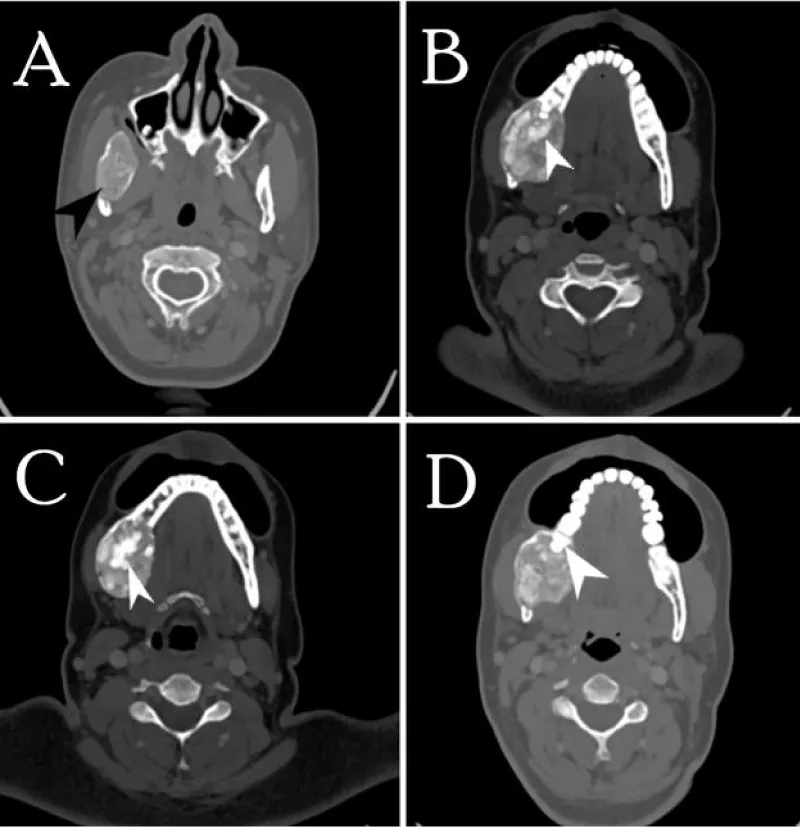

CT scan with contrast was recommended to elicit the extent of the lesion and to characterize the radiological features. It showed a large well corticated, sharply marginated mixed density expansile lesion involving the ramus and body of mandible reaching up to the root of the right lower molar tooth. There was no evidence of cortical break, destruction, or erosion of involved bone. Few intra-lesional hyperdense areas were seen representing calcific foci/ cementing material (Figures 4-6).

In the Radiological aspect, initially, the cemento-ossifying fibroma appears as a well-defined radiolucent lesion with no evidence of internal radio densities. As the tumor progresses, there is evidence of calcification so that the radiolucent area opacifies, and eventually, the lesion appears as a lobulated almost complete radiopaque mass in the mature stage. An important diagnostic feature of cemento-ossifying fibroma is the expansion of lesions equally in all directions and present as a round tumor mass. The cortical plate may be expanded, displaced, thinned out, and remains intact. Teeth adjacent to or involved in the lesion may be displaced but resorption is not associated with this tumor [3,4,6,9]. In our case the tumor was large well corticated, sharply marginated mixed density with high densities representing calcific foci/cementing material, expansile lesion with no evidence of bone destruction or cortical break.